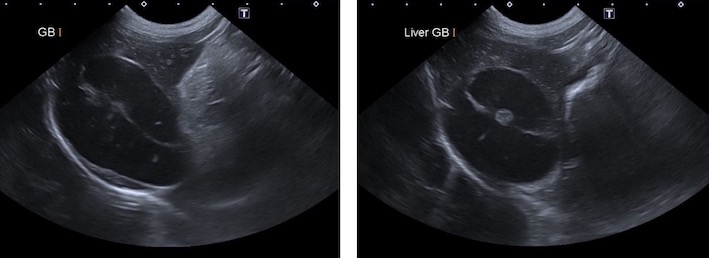

超音波検査画像です。

胆嚢の中に「キウイフルーツパターン」というキウイフルーツのような模様が見えた時、胆嚢粘液嚢腫を強く疑います。

総胆管の拡張も認められ、十二指腸の開口部で閉塞を起こしている可能性が考えられました。